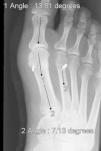

In another 4 cases, we have had problems specific to this technique during follow-up. Two of them with stress fracture of the second metatarsal, at the level of the orifice made to pass the oblong button, both of which were recorded at the 6th week timepoint, mainly due to the clinical symptoms, not only due to the fact that the pain had failed to improve, but also because of increased pain on weight-bearing, especially on palpation, and very selectively in the area where the button had passed through the 2nd metatarsal, since on X-ray, the fracture had not been seen to have shifted. They required another 6 weeks without weight-bearing for full clinical (disappearance of pain) and radiological healing (increased cortical thickening that confirmed our clinical suspicion), and in another two cases, rupture of the oblong button system with migration of this system and loss of reduction; one was documented at the 3rd week and another one at week 6. These last two cases required re-intervention of the patient to remove the material and perform a classical technique.

With respect to the other two cases, the MTR system ruptured and reduction was lost, the implant migrated, and pain made it necessary to operate on the patients again (Figs. 5 and 6). These complications occurred in a 43-year-old male, between the 2nd and 3rd week, which forced him to go to the Emergency Room where it was diagnosed. The other was the case of a 38-year-old female, at the follow-up visit after 3 months. In both cases, they were fairly active people and they have obviously meant that the system failed, since without actually fracturing the bone, the suture gave way, leaving the loose implant to migrate to above the second metatarsal in both cases. It is more than likely that the loss of reduction was because MTR rupture took place before healing was strong enough to maintain reduction; in fact, these ruptures occurred early. These last two complications beg the question of whether they were the result of a mechanical failure (material in poor condition in these cases in particular) or biomechanical failure (inability to assume heavy weight-bearing in individuals with heavy foot use). To be able to discern between once cause and another will call for long-term follow-ups and longer case series to find trends or patterns that can account for these failures.

These 4 complications took place in cases 4, 5, 7, and 9 of our series in chronological order; that is to say, in all likelihood the placement of the hole for the MTR system in these first cases was not the correct one, above all, thinking of the stress fractures we have had. As a result of these first complications, we subsequently ensured optimal placement of the orifice in the anteroposterior, mediolateral, and craniocaudal planes in order for this system to work properly, protected by cortical bone on all edges, which we believe has been key to overcoming part of this issue; that is, as with all techniques, it calls for an adequate learning curve.